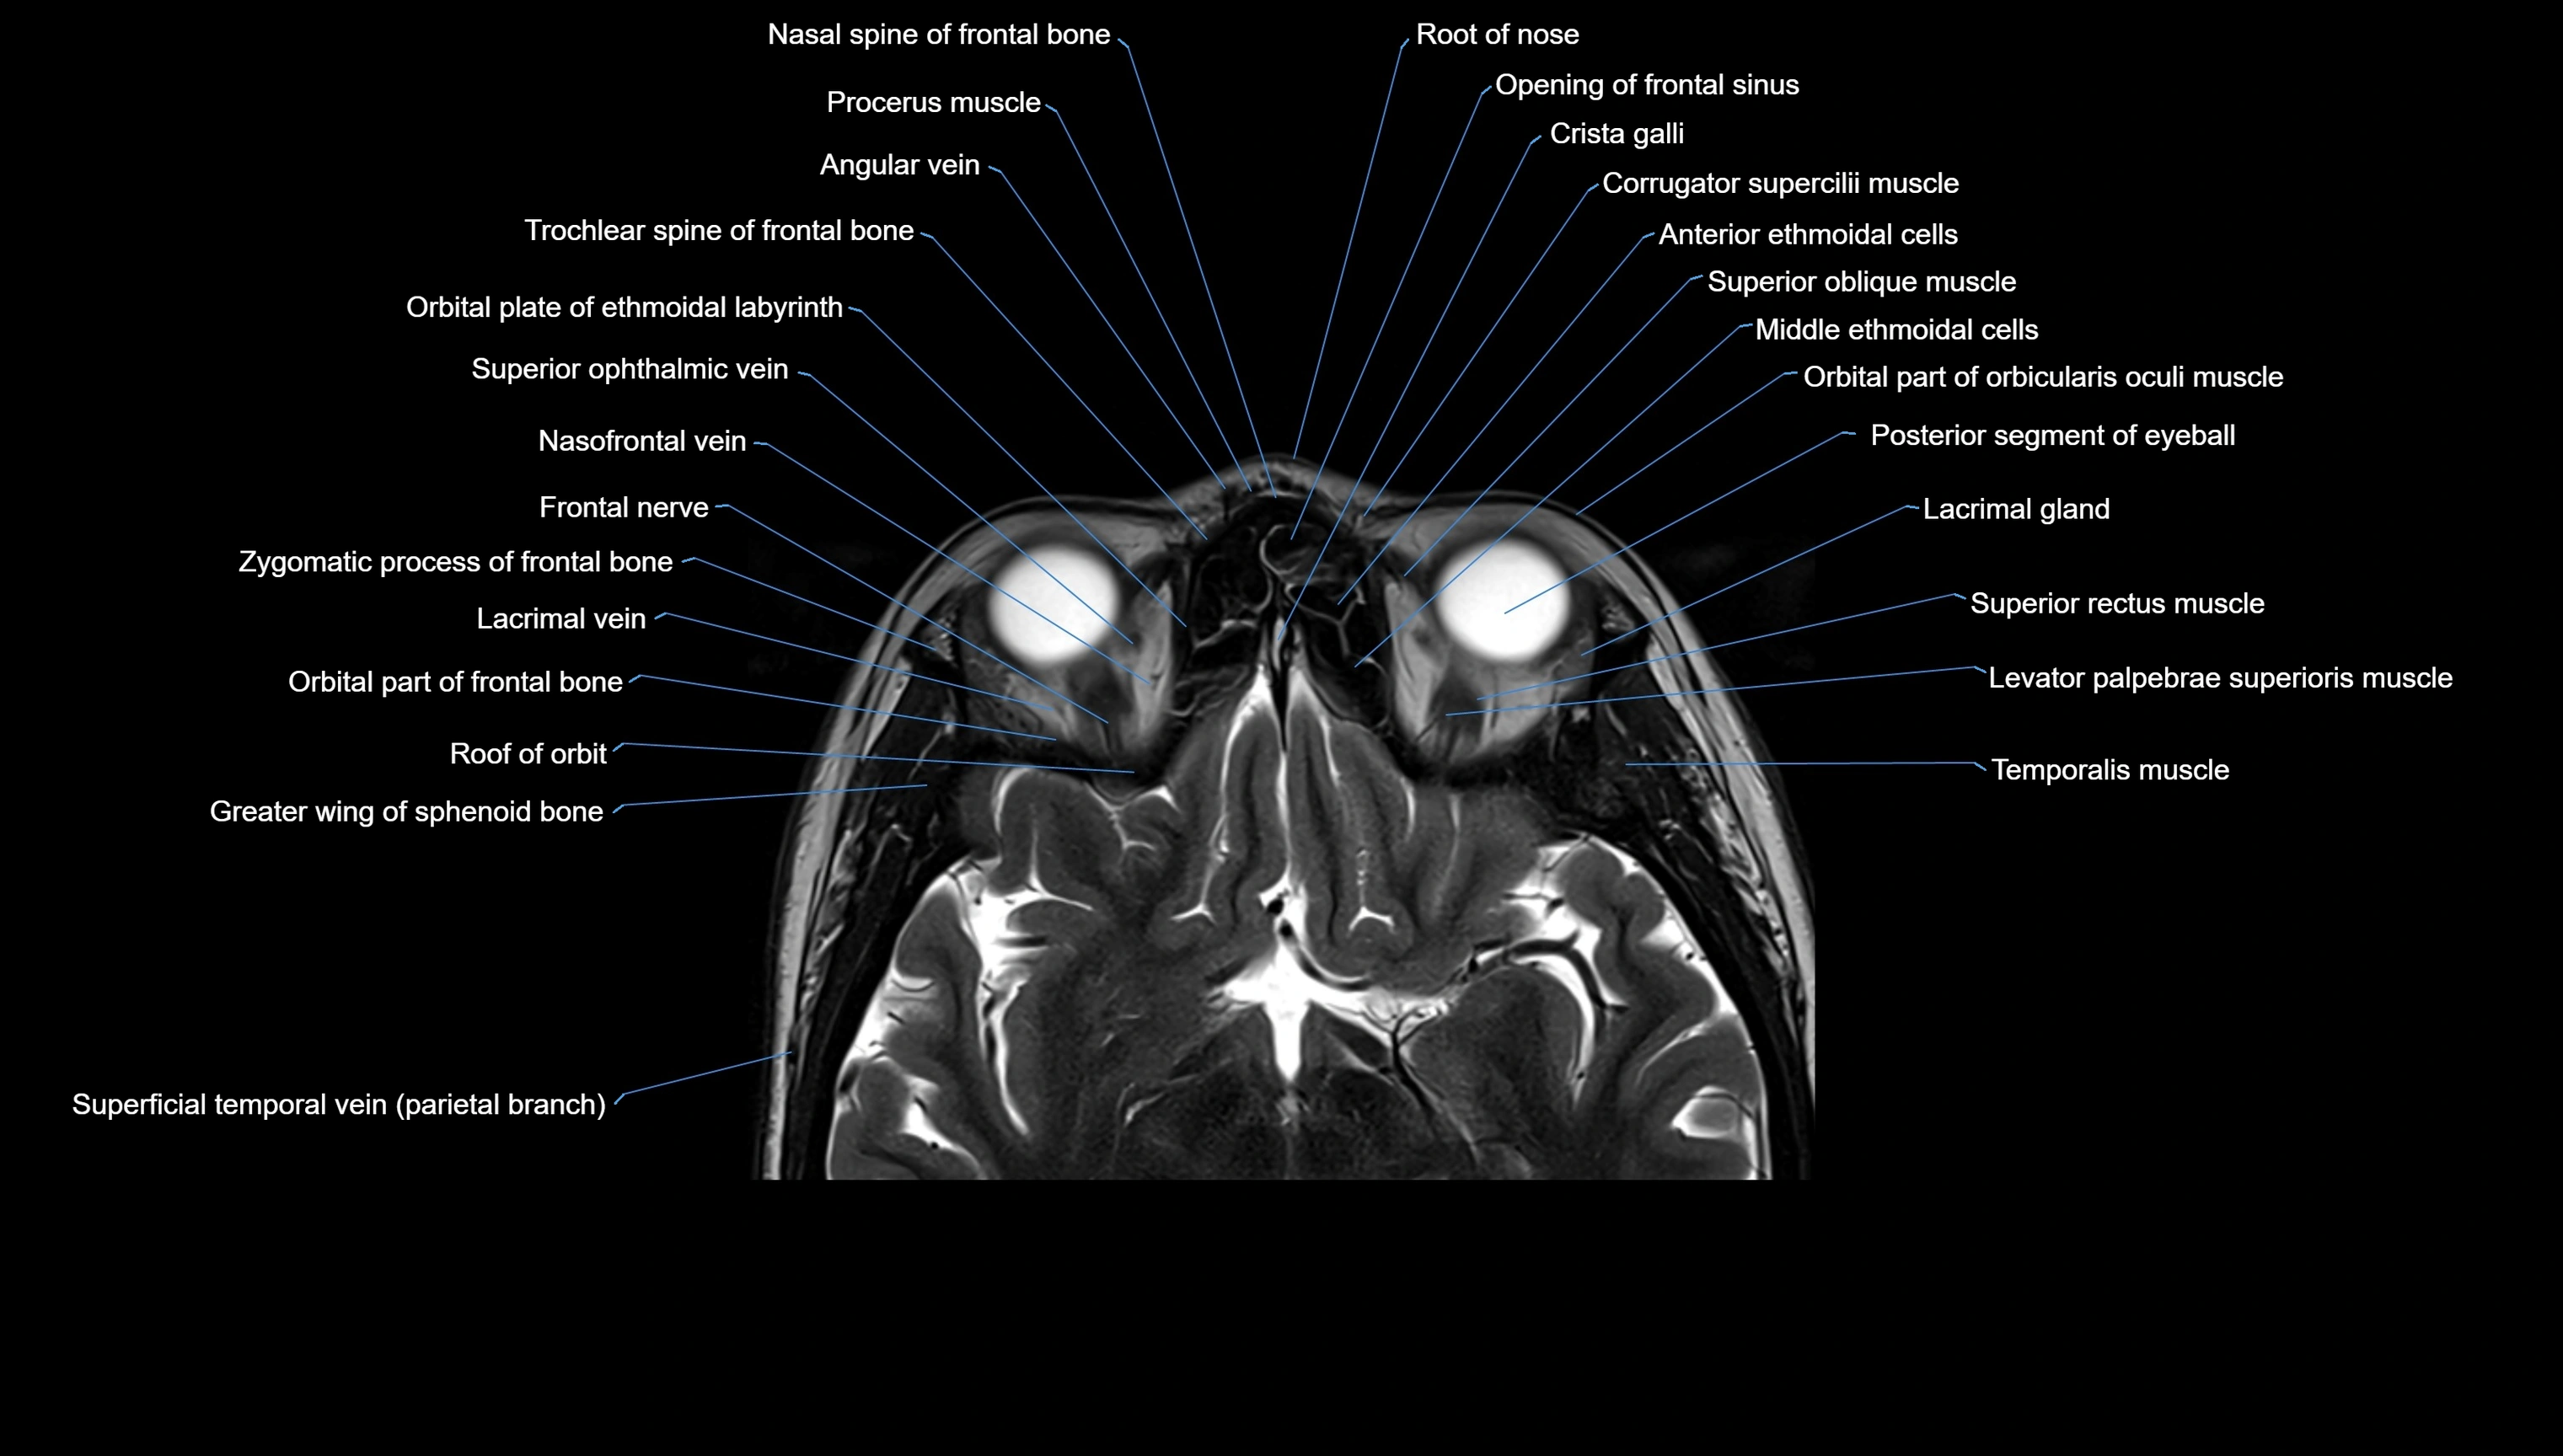

MRI images